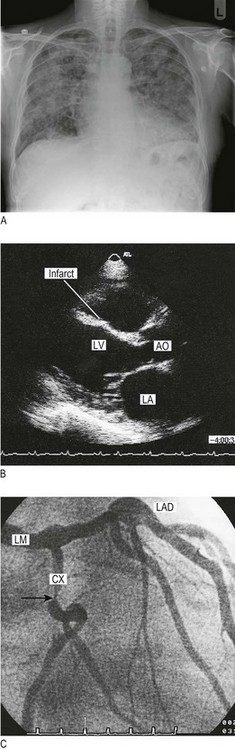

Fig. 6.34 Cardiovascular imaging.

(A) Chest X-ray in heart failure. This shows cardiomegaly with patchy alveolar shadowing of pulmonary oedema and Kerley B lines (engorged lymphatics) at the periphery of both lungs. (B) Transthoracic echocardiogram in parasternal long-axis view. This shows thinning of the interventricular septum, which has an irregular shape and bright echoes indicating fibrous scarring. This is the site of an old infarct. LA, left atrium; LV, left ventricle; AO, aortic root. (C) Coronary angiography. The arrow indicates a severe discrete stenosis in the circumflex coronary artery. LM, left main; LAD, left anterior descending; CX, circumflex.

Echocardiography: Echocardiography uses high-frequency sound waves to evaluate valve abnormalities, left ventricular function and blood flow (Doppler echocardiography). Most scans are performed through the anterior chest wall (transthoracic) (Fig. 6.34B). Transoesophageal echocardiography requires sedation, but gives high resolution of posterior structures, e.g. left atrium, tricuspid valve and descending aorta.

Cardiac catheterisation: A fine catheter is introduced under local anaesthetic via a peripheral artery (usually the brachial or femoral) and advanced to the heart under X-ray guidance. Although measurements of intracardiac pressures and therefore estimates of valvular and cardiac function are possible, the primary application of this technique is coronary arterial imaging, using contrast medium. This is performed to inform revascularisation, either by coronary angioplasty or bypass grafting (Fig. 6.34C).